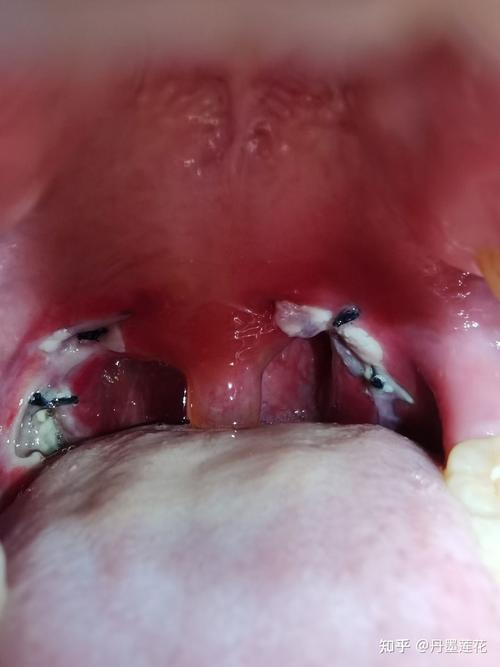

扁桃体术后恢复过程图

扁桃体术后恢复过程图,扁桃体术后化脓图片

扁桃体术后化脓图片

扁桃体术后图片

扁桃体术后恢复图片

扁桃体术后白膜图片

扁桃体术后白膜